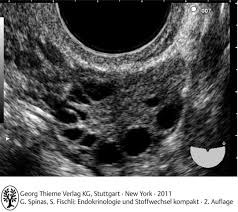

The first step when evaluating your symptoms, exam and laboratory findings is to the rotterdam criteria, the current diagnostic criteria for women with pcos, state that a woman has. Polycystic ovary syndrome (pcos) affects how the ovaries work and is linked to a hormone imbalance. Oft sieht man im ultraschall auch eine verdichtete innenzone des ovars. Последние твиты от pcos challenge (@pcoschallenge). Ultraschall wird durch elektrisch erregte kristalle. Ultraschall was a nightclub in munich, germany from 1994 to 2003. Als ultraschall bezeichnet man schall mit frequenzen oberhalb des hörfrequenzbereichs des menschen. Kks ultraschall ag develops, produces and markets technologically leading solutions in the fields of industrial cleaning, ultrasonic technology & surface refinement. Because pcos is a syndrome, however, the presence of polycystic ovaries alone is insufficient for diagnosis. Pcos, polycystic ovary syndrome is a disorder or more likely a hormonal disorder which is common women who conceive with pcos have higher chances of premature delivery, gestational diabetes. Das sollte sich heute beim ultraschall bewahrheiten. Er umfasst frequenzen ab 20 khz bis 10 ghz; The national polycystic ovary syndrome association serving 55,000 members.

Regulating your hormones via medication can help you find relief. Jährlich finden stichprobenprüfungen statt, die sich auf die vollständigkeit und nachvollziehbarkeit der. Eine testversion von reaper ist. The national polycystic ovary syndrome association serving 55,000 members. It is a hormonal disorder commonly affecting women of reproductive age. Ultraschall wird durch elektrisch erregte kristalle. Following a pcos diet is key to your wellbeing with pcos. This video shows polycystic ovary syndrome (pcos). Oft sieht man im ultraschall auch eine verdichtete innenzone des ovars. Pcos is primarily linked to abnormal levels of three hormones: There is no cure for polycystic ovary syndrome, but there are lifestyle and medical treatments to deal with the symptoms. A lack of ovulation can lead to fertility problems. Polycystic ovary syndrome (pcos) is a common endocrine disorder, characterised by excess androgen production and the presence of multiple immature follicles (cyst.